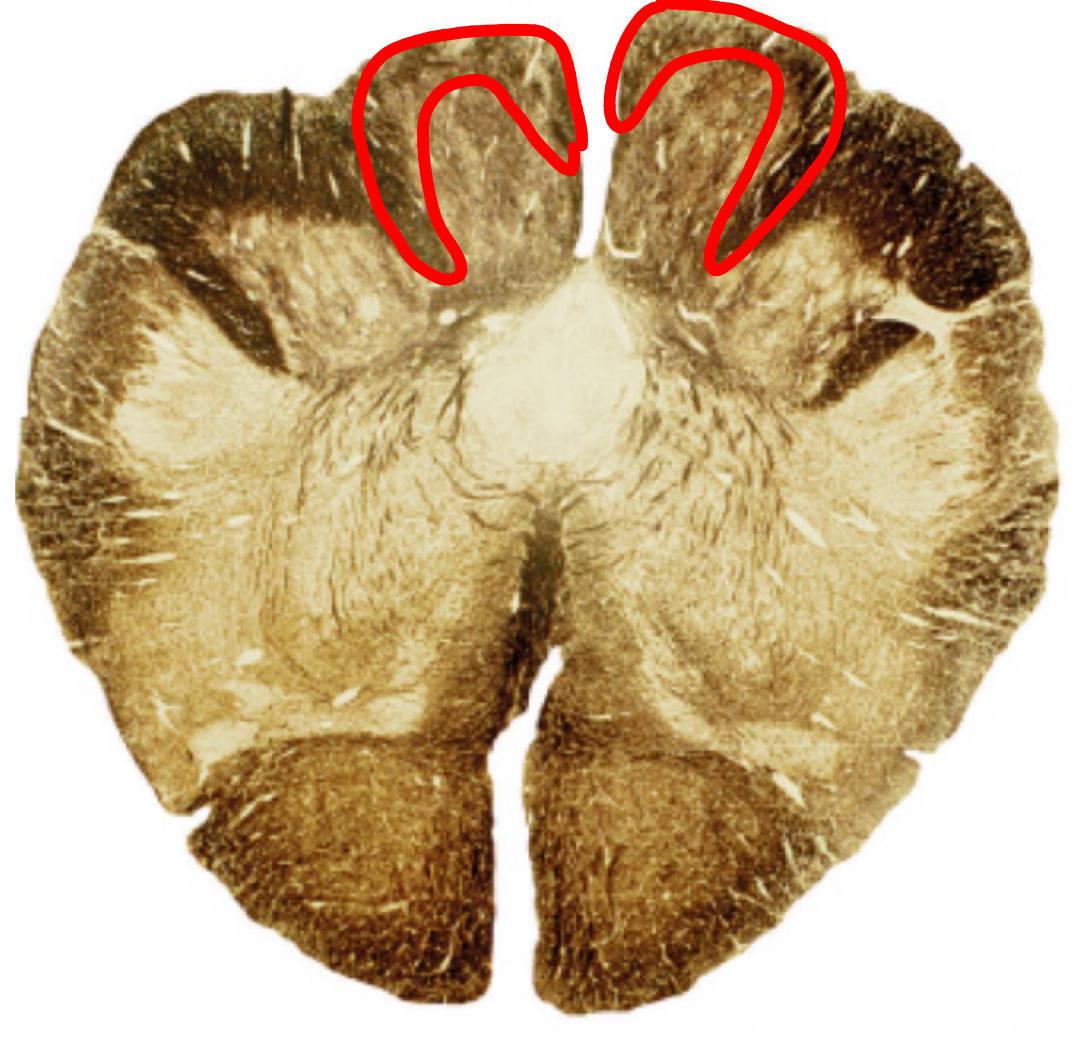

pontine nuclei caudal pons

corticospinal fibers caudal pons

middle cerebellar peduncle caudal pons